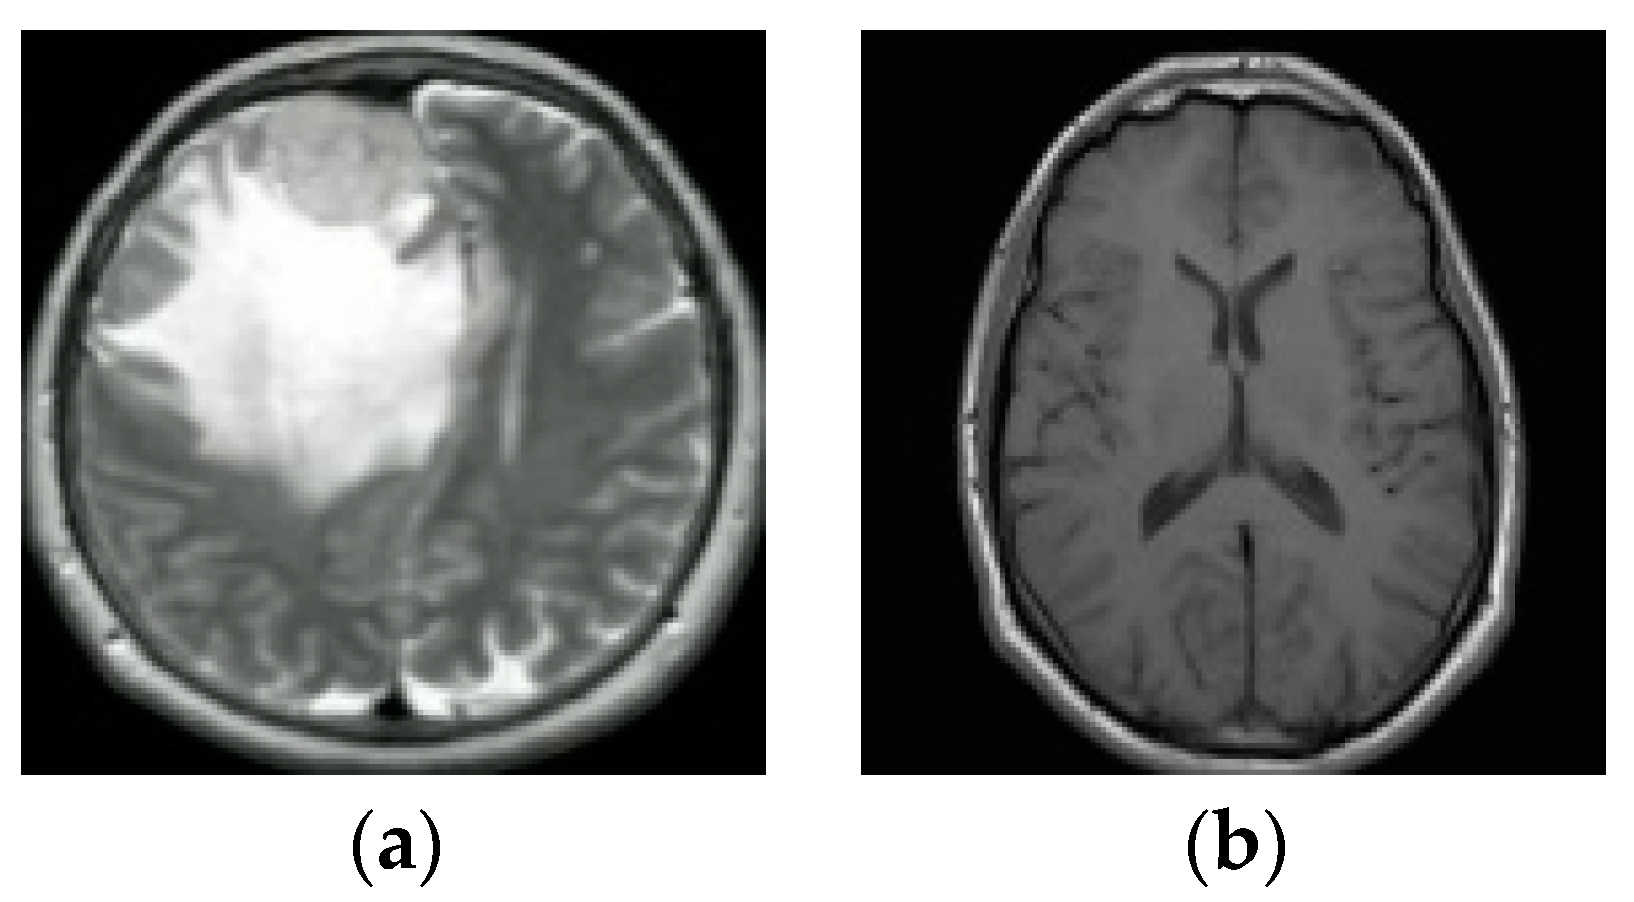

A growth that may adversely impact a person’s life is a brain tumor, which can appear in the tissues enclosing the brain or skull. Two characteristics can identify a benign or malignant growth. While secondary tumors, also referred to as brain metastasis tumors, are typically formed from tumors outside the brain, primary cancers start inside the brain. Meningiomas, pituitary adenomas, and gliomas are the three most common primary brain tumors. The brain and spinal cord membrane layers are the origin of meningiomas, a type of tumor that grows slowly. Cancerous cells that arise in the pituitary gland are referred to as pituitary adenomas [1]. The brain tissue is compressed by the irregular growth of these tumors. Malignant tumors, in comparison with benign tumors, grow unevenly and damage the tissues around them. Surgical techniques are frequently employed in the treatment of brain tumors [2]. Because MRI is non-interfering, it is preferred over computed tomography (CT), positron emission tomography (PMT), and x-rays [3]. It is estimated that 79,340 Americans aged 40 and older will be diagnosed with a primary brain tumor by 2023. It is estimated that one million Americans suffer from primary brain tumors; of these, 72% are benign tumors and 28% are malignant. The adults with primary brain tumors typically have meningioma (46.1%), glioblastoma (16.4%), and pituitary tumors (14.5%) [4,5]. Biopsies are taken for analysis after the tumor is found using standard medical techniques like MRI. The first test used in medicine to find cancer is MRI [6,7]. Two MRI pictures of two distinct brains are shown in Figure 1.

Figure 1. MRI scans performed on two different brains. (a) On the left is a tumor, and (b) on the right is a healthy brain [8].